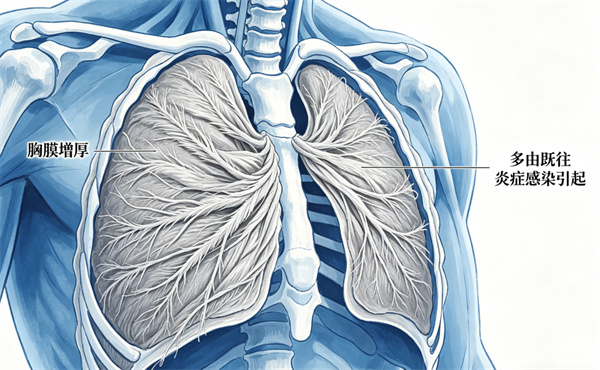

5胸膜增厚

多由既往胸膜炎、肺部感染引起。

多数人无症状、无需处理。